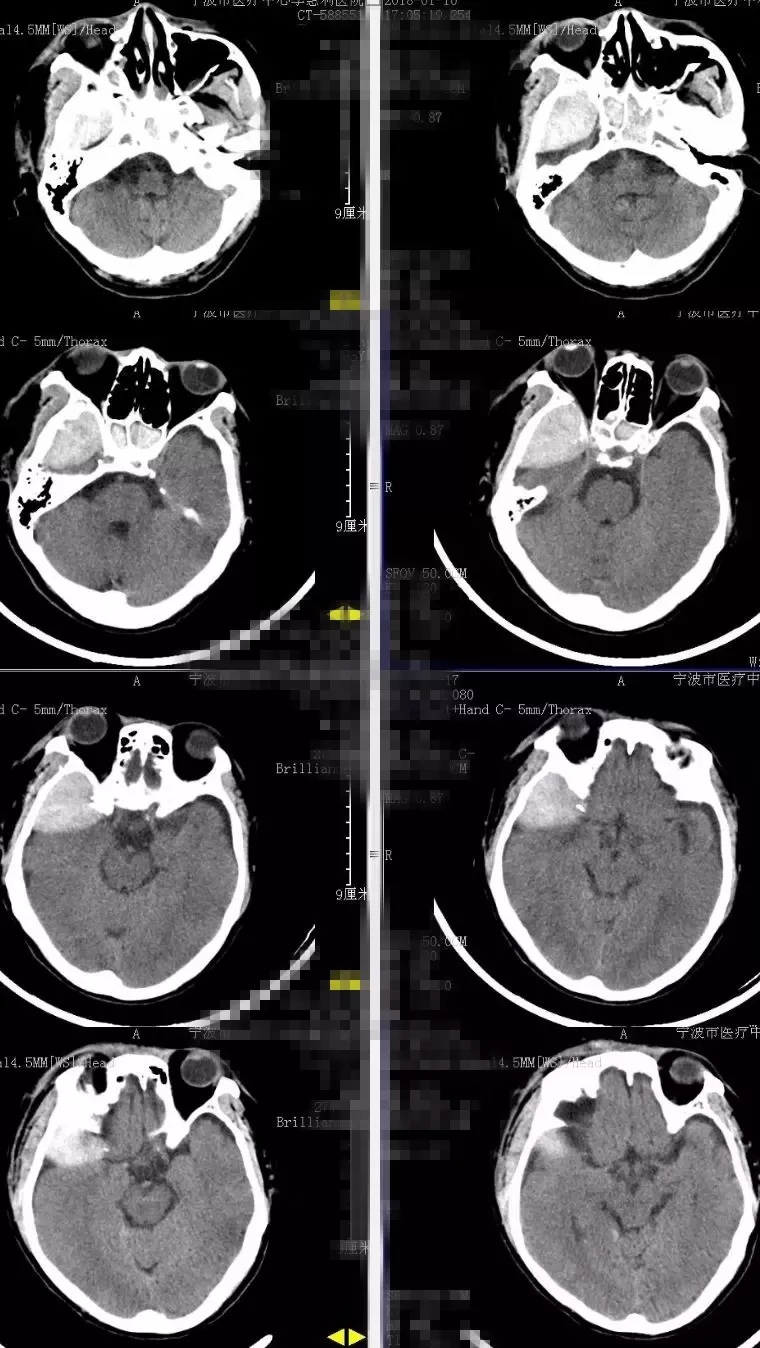

鉴于患者有轻微头痛头晕,病情稳定,颅高压尚可,入院后完善各项辅助检查,预防感染、止血、神经营养等保守治疗。拟头部情况稳定后,转骨科行右肱骨手术治疗。保守治疗一周后(2018-1-17)头颅CT显示右颞硬膜外血肿基本同前(图2),遂继续保守治疗。2018-1-22及27日再次复查头颅CT,显示右颞硬膜外血肿较前逐渐吸收,密度降低(图3)。

图2. 2018-1-17头颅CT显示右颞硬膜外血肿基本同前,密度稍降低。

图3. 2018-1-22及2018-1-27再次复查头颅CT显示右颞硬膜外血肿较前逐渐吸收,密度降低。